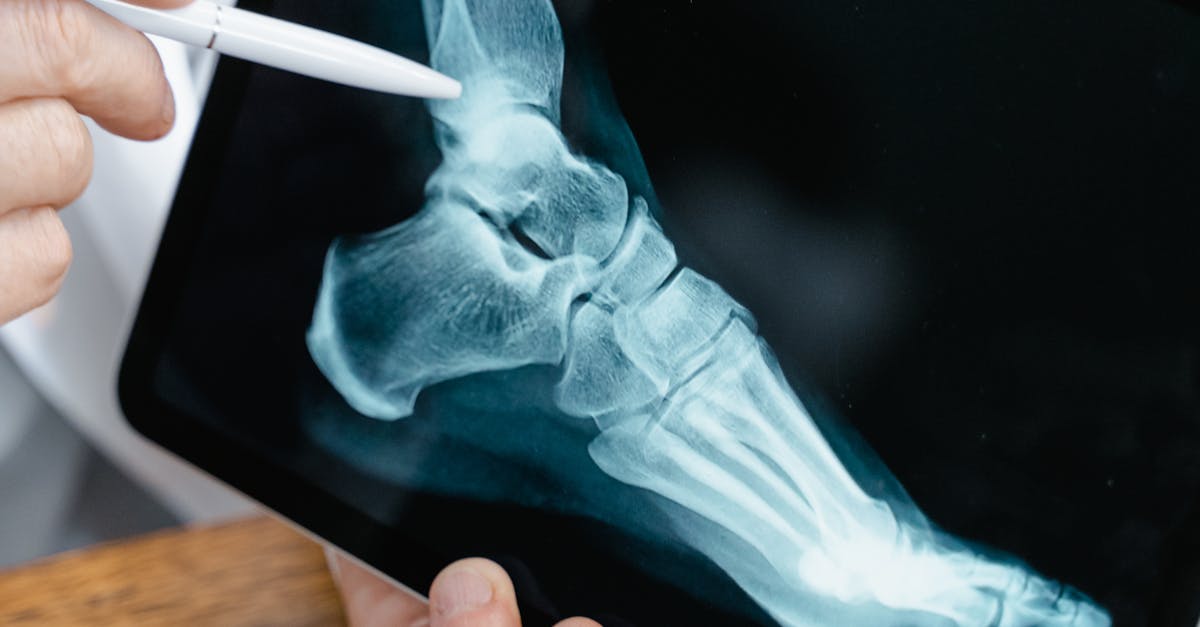

10. Foot Pronation and Supination Patterns - The Ground-Up Effect

Foot posture abnormalities, particularly excessive pronation and supination patterns, represent fundamental postural deviations that create far-reaching effects throughout the entire kinetic chain due to the foot's role as the primary interface between the body and ground. Excessive pronation, characterized by flattening of the medial longitudinal arch, calcaneal eversion, and forefoot abduction, affects approximately 20-25% of the population and creates significant biomechanical dysfunction during weight-bearing activities. Conversely, excessive supination, involving high arches, calcaneal inversion, and reduced shock absorption capacity, affects a smaller but significant portion of the population and creates its own unique set of compensatory patterns. Research utilizing pressure plate analysis and three-dimensional gait analysis has revealed that abnormal foot posture significantly alters ground reaction forces and joint loading patterns throughout the lower extremity. Excessive pronation creates internal rotation moments that travel proximally through the kinetic chain, contributing to tibial internal rotation, knee valgus, femoral internal rotation, and anterior pelvic tilt. Clinical studies have established strong correlations between excessive pronation and the development of plantar fasciitis, posterior tibial tendon dysfunction, medial knee pain, and hip internal rotation syndrome. Conversely, excessive supination reduces the foot's natural shock absorption capacity, increasing the transmission of impact forces to proximal structures and contributing to lateral ankle instability, iliotibial band syndrome, and stress fractures. The postural implications extend beyond the lower extremity, as altered foot mechanics can influence pelvic positioning, spinal alignment, and even upper extremity function through compensatory mechanisms. Furthermore, research has